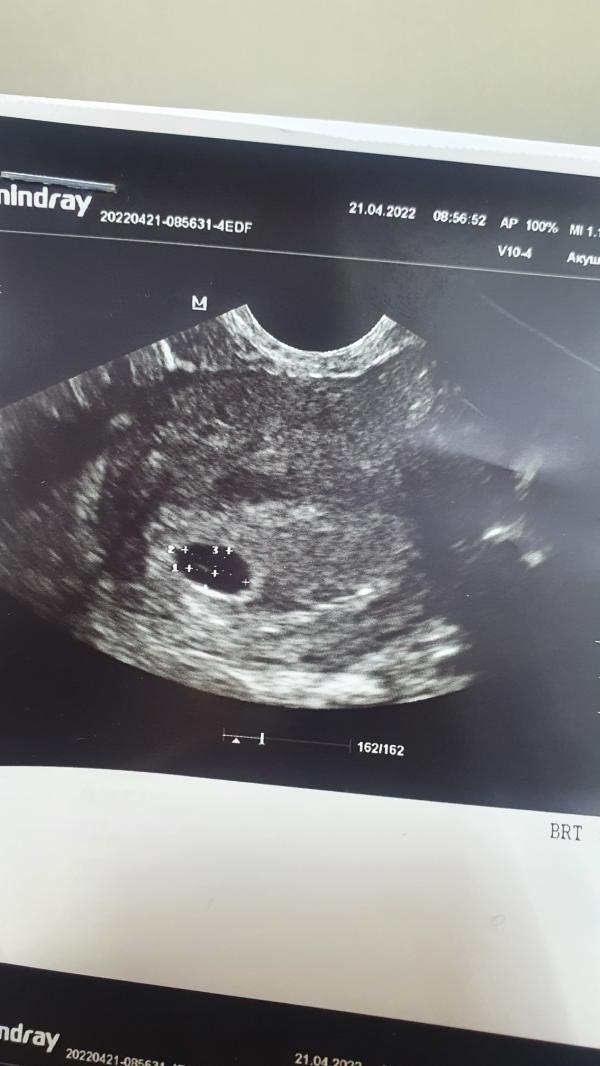

Первая фотокарточка. Сказали что все хорошо. Через пару недель пригласили слушать сердечко🤗